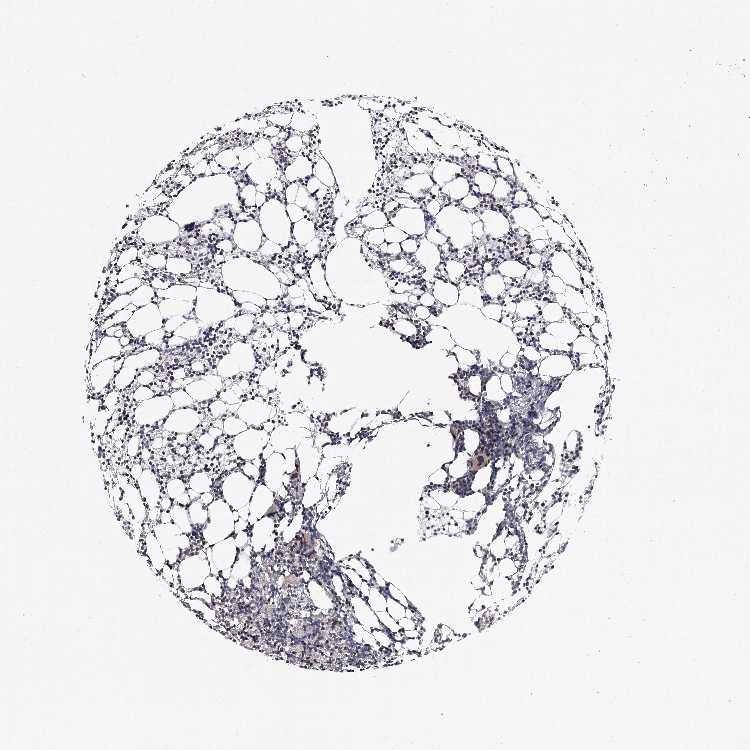

BONE MARROW - Antibody stainingi

Antibody staining in the annotated cell types in the current human tissue is reported as not detected, low, medium, or high, based on conventional immunohistochemistry profiling in selected tissues. This score is based on the combination of the staining intensity and fraction of stained cells.

Each image is clickable and will lead to virtual microscopy that enables deeper exploration of all samples and also displays staining intensity scores, fraction scores and subcellular localization as well as patient and tissue information for each sample.

Antibody HPA038981

Hematopoietic cells Low